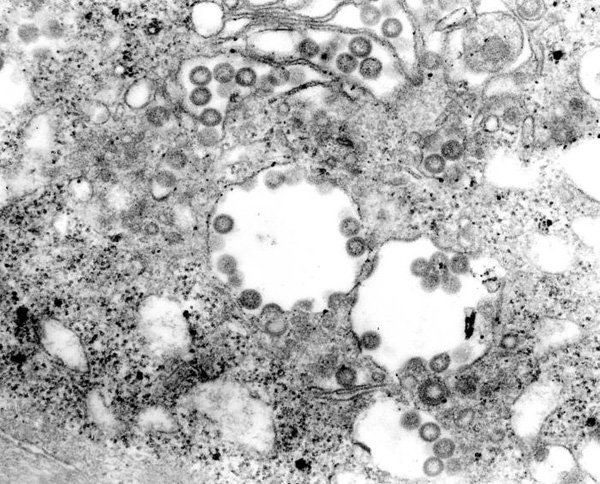

1. Virus Marburg

Virus họ hàng của Ebola hiện được coi là virus đáng sợ nhất đối với loài người. Tên của nó được đặt theo tên của một thị trấn nhỏ, yên bình bên dòng sông Lahn ở bang Hessen, Đức, vốn không liên có liên hệ gì với căn bệnh mà virus gây ra. Virus Marburg thực tế là một virus gây sốt xuất huyết.

Virus Marburg được lây truyền qua tiếp xúc, từ việc người tiếp xúc với những chú khỉ ăn phải những loại hoa quả đang ăn dở từ dơi mang mầm bệnh. Người mắc bệnh sẽ bị virus tấn công vào những bộ phận trọng yếu và những cơ quan chính như gan, thận, phổi, ruột, cơ quan sinh sản, tuyến nước bọt.

Sau khi xâm nhập vào các cơ quan, virus sẽ gây cho người bệnh chứng sốt xuất huyết nặng: co giật và chảy máu các màng nhầy, da và cơ quan nội tạng, với tỉ lệ tử vong từ 50-100% chỉ sau 8-10 ngày.